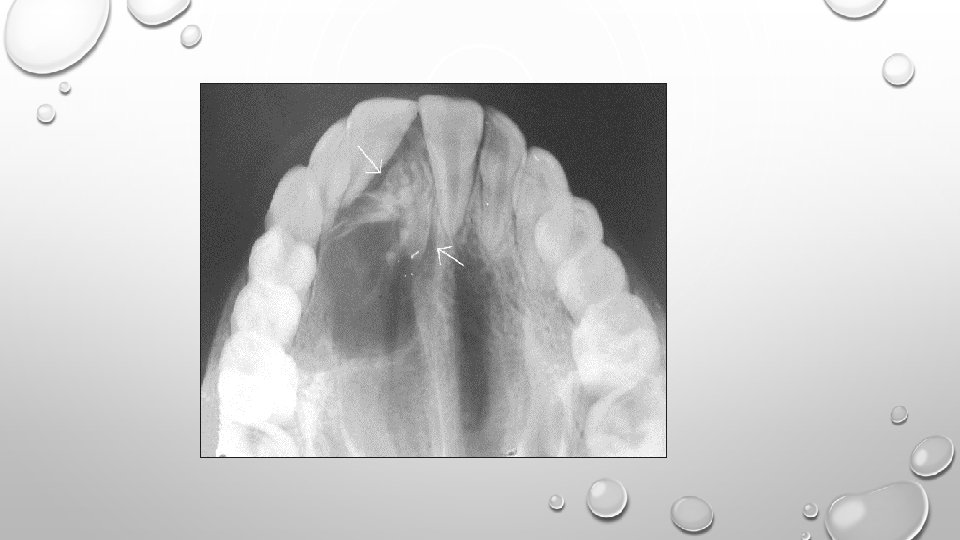

ADENOMATOID ODONTOGENIC TUMOR: • It is an uncommon, benign tumor which makes up approximately 3% of all odontogenic tumors. • It is a slow-growing tumor which is locally invasive, tends to displace teeth and cause mobility. • Usually occurring in the second decade of life, is more frequent in the maxilla than in mandible, mostly in the anterior region. • Enucleation is the treatment of choice.